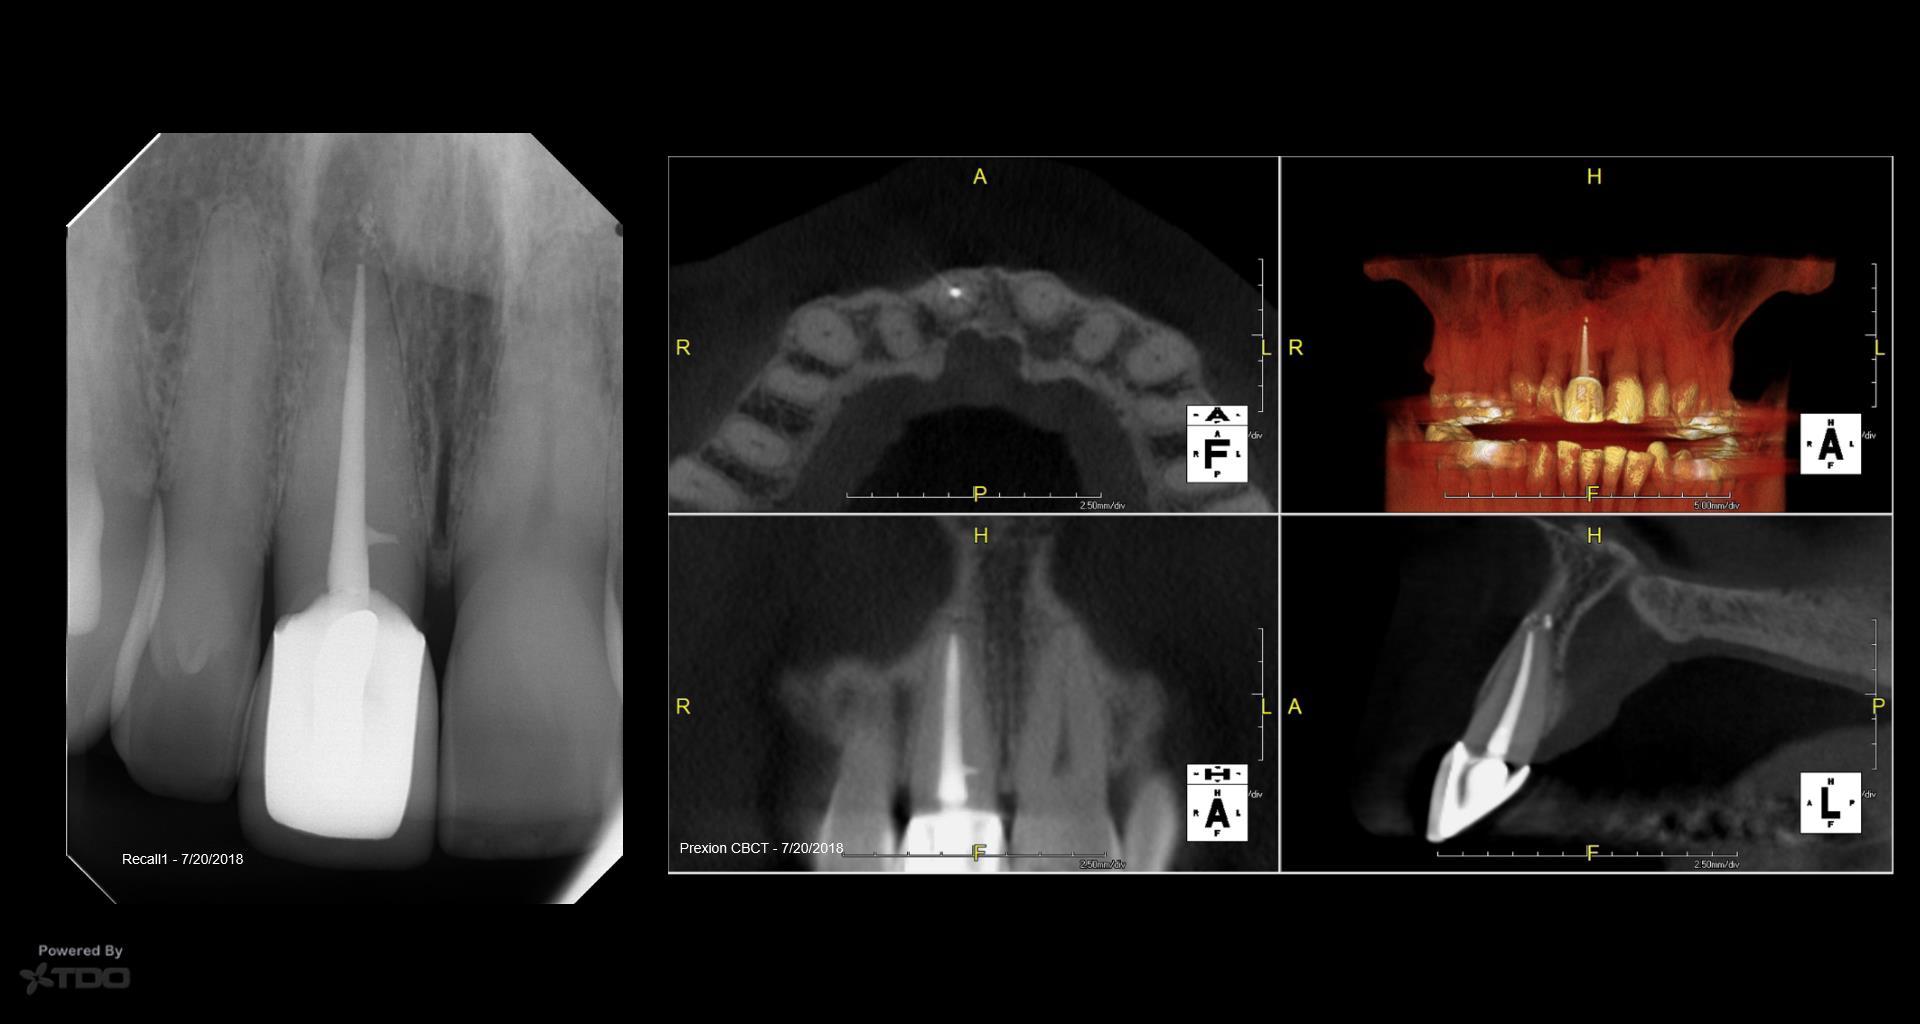

20 yr recall today

Don you just love anterior teeth recalls?